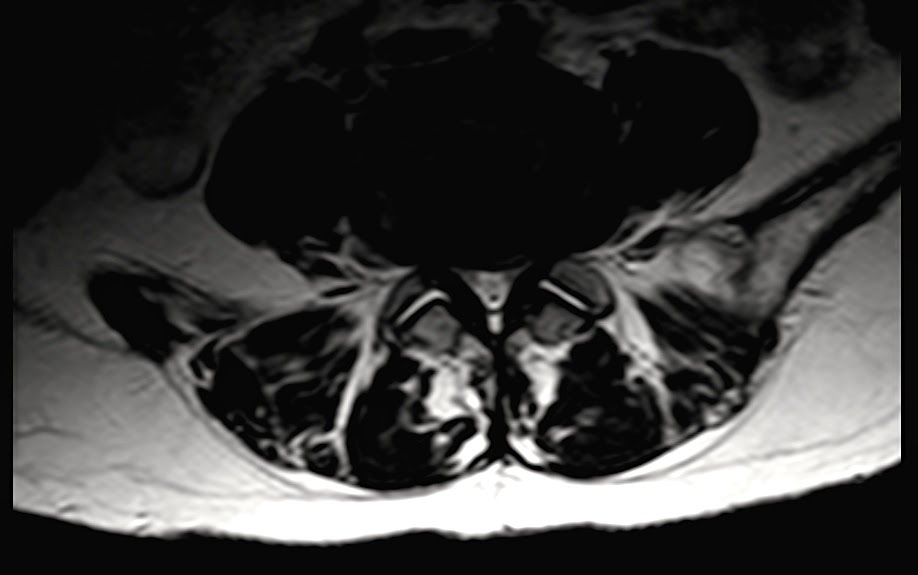

WebLa operación más frecuente es una simple descompresión. Esta intervención consiste en retirar la pared posterior del canal con el fin de ensanchar el conducto vertebral. WebLa lesión de los músculos en la intervención deben seguir un proceso de reparación. Dependiendo del tipo de cirugía, si ha sido con una apertura grande o con microcirugía,. WebLa estenosis lumbar es un estrechamiento del canal raquídeo a expensas de una proliferación ósea que comprime las estructuras nerviosas que contiene. Los.

WebAnimación realizada por Javi Arán.Voz en off: Vere ÁlvarezDr. Bernardo Mosqueira CenturionLes recordamos que pueden seguirnos en nuestra web y redes sociales... WebEstenosis del canal lumbar. La lumbalgia y la debilidad en las piernas pueden ser a causa de una estenosis del canal lumbar. Conoce como puede diagnosticarse y cuáles son los.